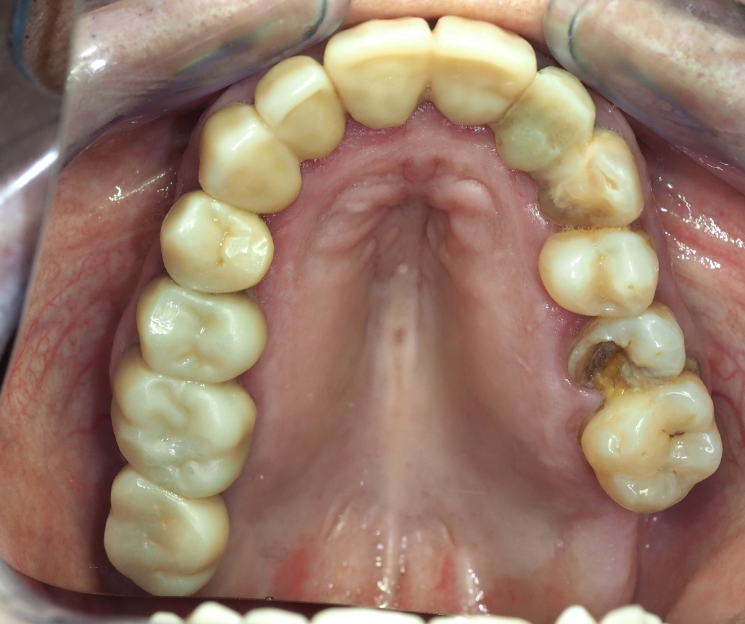

- Paciente: Paciente sin patologías relevantes 39 años.

- Diente afectado: 25 (primer premolar superior izquierdo).

- Diagnóstico: Indicación de exodoncia.

- Extracción atraumática: Se realizó la exodoncia del diente 25, preservando al máximo las estructuras óseas.